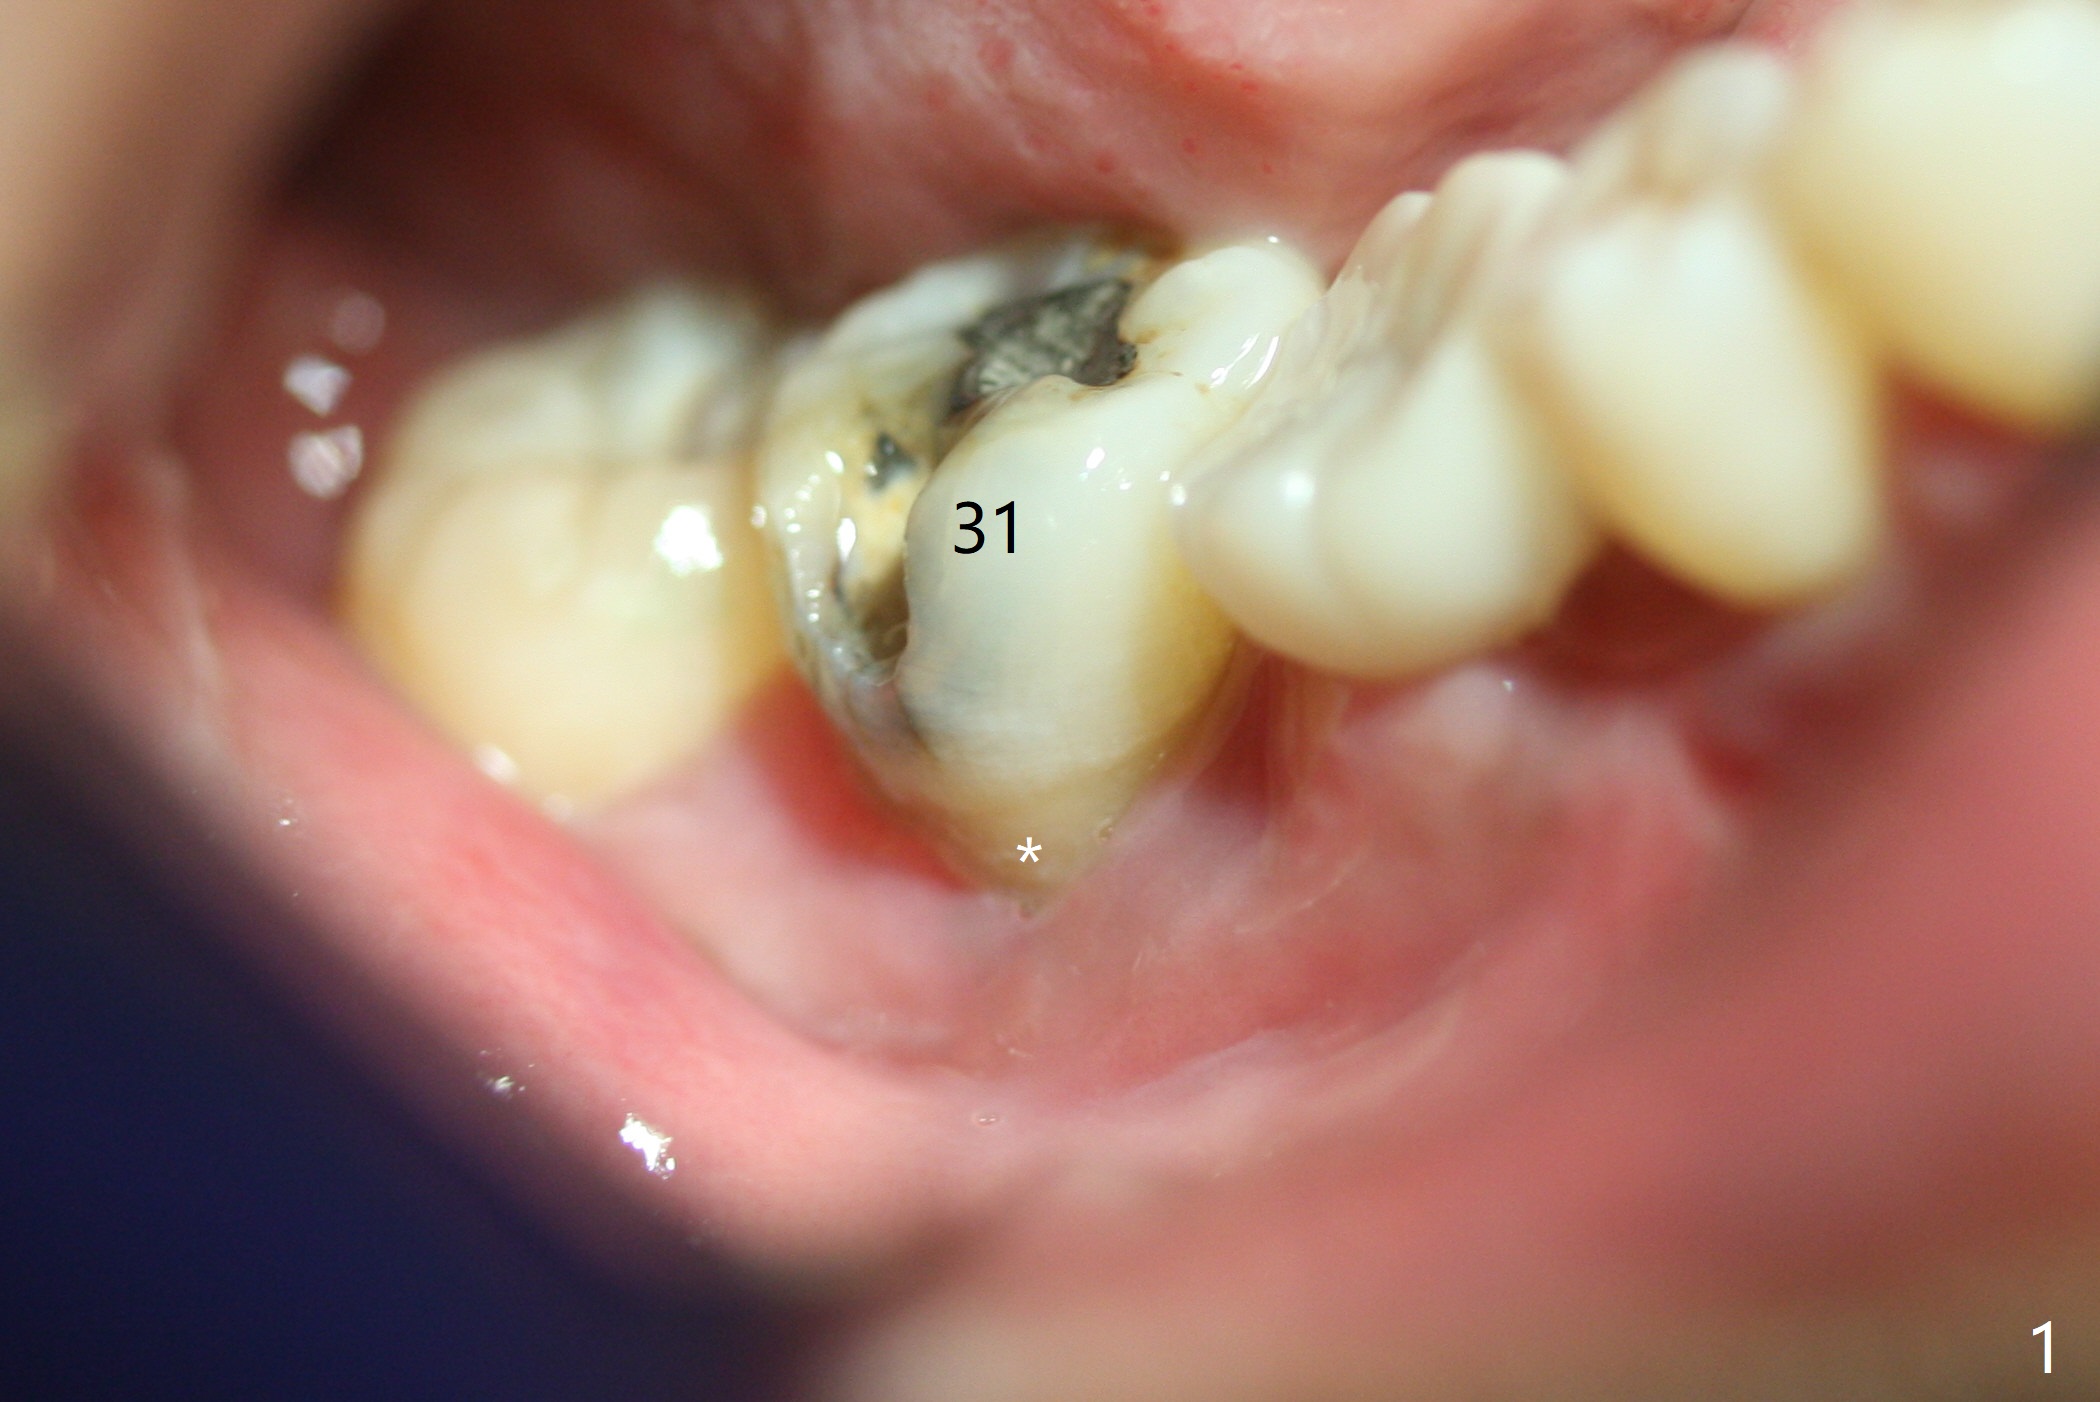

Although the bony socket is shallow, the soft tissue one remains deep at #31 with gingival recession (Fig.1 *). The deep soft tissue socket with hemorrhage after extraction presents difficulty in debridement of granulation tissue apically. After placement of allograft (Fig.3 *) and overlying collagen membrane (Fig.2 C), the socket is closed with 4-0 Chromic gut suture. In fact, there is ~ 2 mm granulation tissue left (Fig.4 red (yellow line: upper border of the Inferior Alveolar Canal)). To reduce socket shrinkage, the tooth #32 is not extracted. The collagen membrane has lost 1 week postop (Fig.5). More sutures should have been used, preferably using Human Amnion Chorion Allgraft as a membrane. The latter promotes wound healing. The bone graft also seems to have lost in 8.5 months (Fig.6). A short implant will be placed mesially and obliquely (Fig.7).